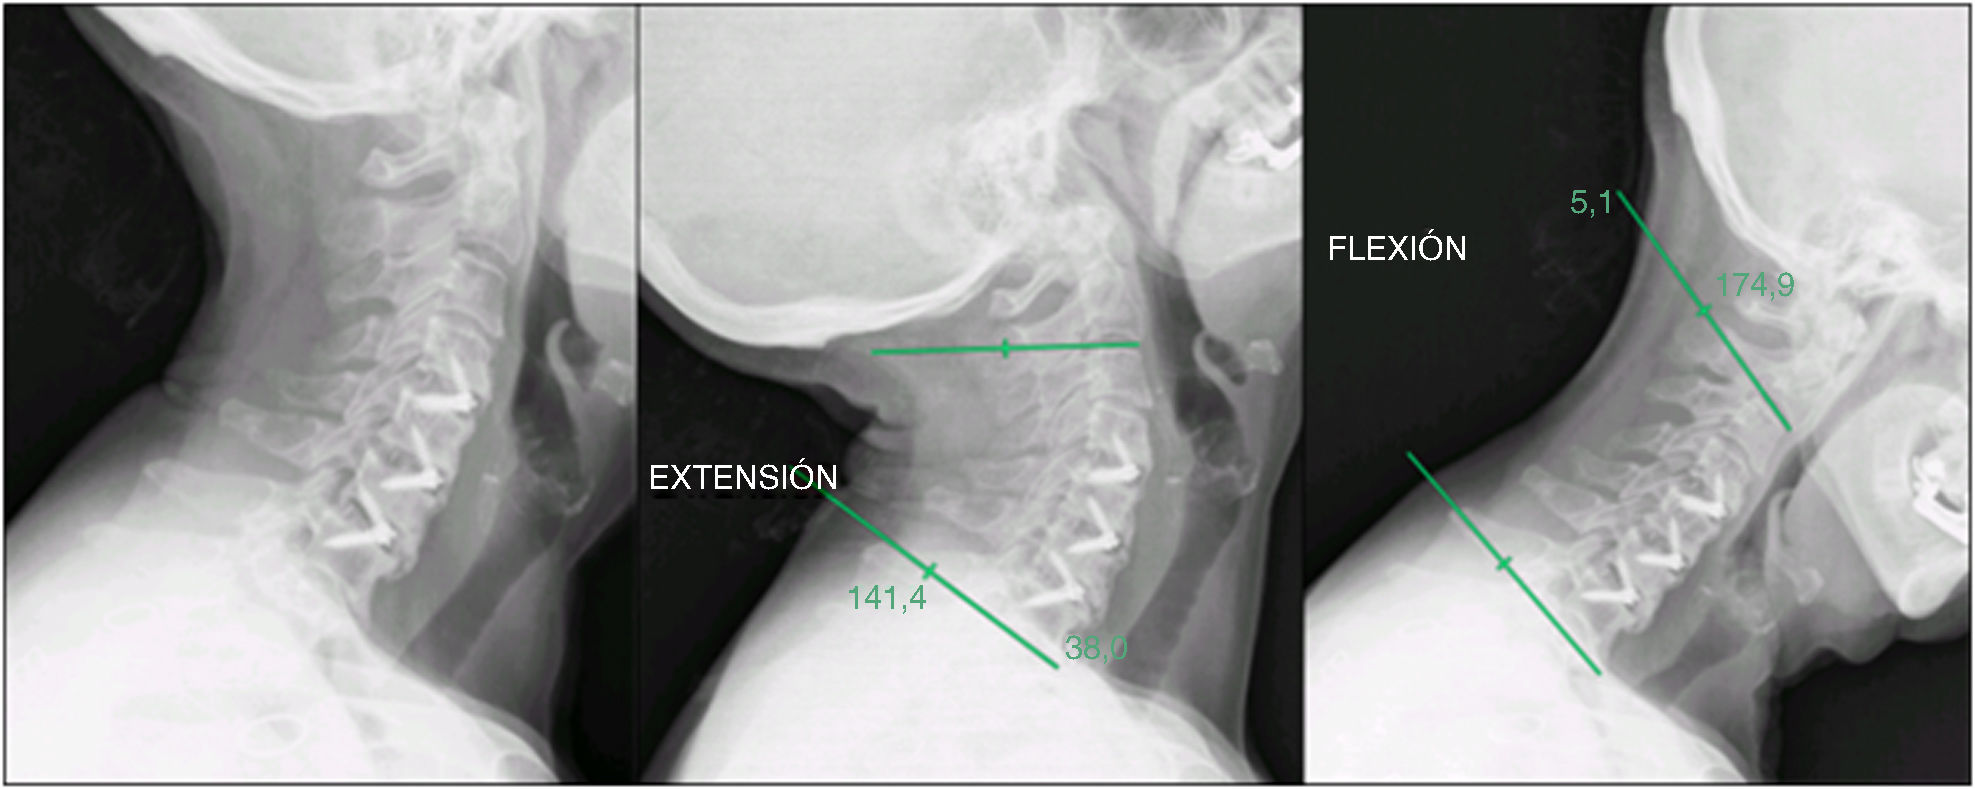

Criterios de valoración radiológicosLas radiografías dinámicas de flexión/extensión (fig. 3) no demostraron movimiento segmentario en ningún caso en los niveles operados en el seguimiento a largo plazo. Las imágenes de resonancia magnética (RM) pre- y postoperatorias representativas (fig. 4) confirmaron una descompresión adecuada con un artefacto de susceptibilidad mínimo.

Caso 37: radiografías dinámicas de flexión/extensión. (A) Vista lateral en flexión en el seguimiento a largo plazo que no muestra movimiento segmentario en los niveles operados. (B) Vista lateral en extensión en el seguimiento a largo plazo que confirma la ausencia de inestabilidad y demuestra una construcción intercorporal estable.